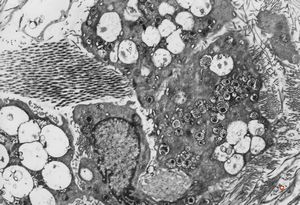

M,40y. | granular cell tumor

F,30y. | granular cell tumor